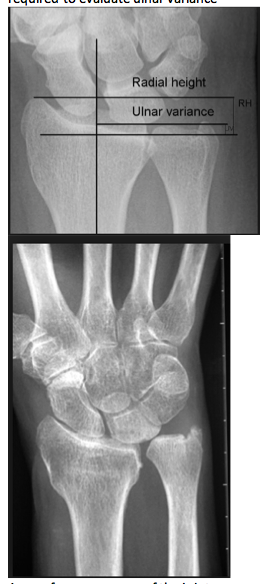

How is the load distribution in the wrist affected by ulnar variance?

What conditions are associated with the pathological finding of this XR? What would you expect to find on physical exam?

Ulnar Positive Variance

What conditions are associated with the pathological finding of this XR?

Ulnar Negative Variance

How does position of the forearm affect ulnar variance?

A pronated grip view is the best to determine your ulnar varience

Pathophysiology of altered ulnar variance